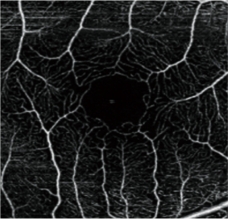

血流OCT在精細(xì)模式下可提供高分辨率圖像,以助于提高診斷率。

自動全景成像(可達(dá)12 x 12 mm)

本軟件可自動合成區(qū)域范圍可達(dá)12 x 12 mm的全景圖像。

圖片由鹿兒島大學(xué)醫(yī)院(Kagoshima University Hospital)提供